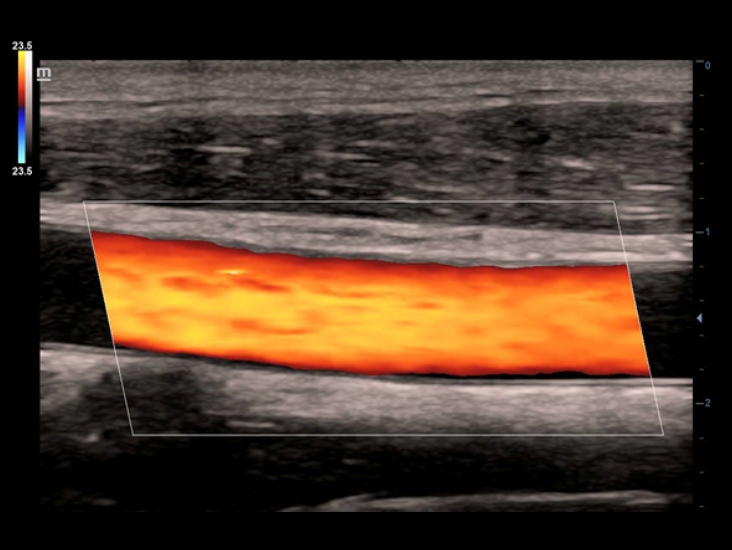

Transductores ComboWave

En comparaciĂłn con los sensores tradicionales, los transductores ComboWave utilizan un nuevo tipo de material piezoelĂ©ctrico compuesto que optimiza notablemente el espectro acĂșstico y reduce la impedancia acĂșstica. AdemĂĄs de integrarse con la tecnologĂa Ășnica 3T de Mindray, los transductores lineales ComboWave ofrecen un rendimiento sobresaliente con una gran uniformidad y resoluciĂłn de imagen en ecografĂas vasculares, de tiroides, de mama, etc.